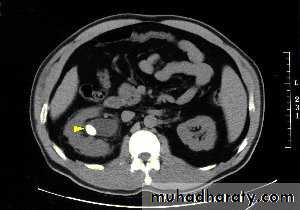

CT scanstones in kidneys

High density renal stonesStage horn calculus KUB filmsradio opaque stones